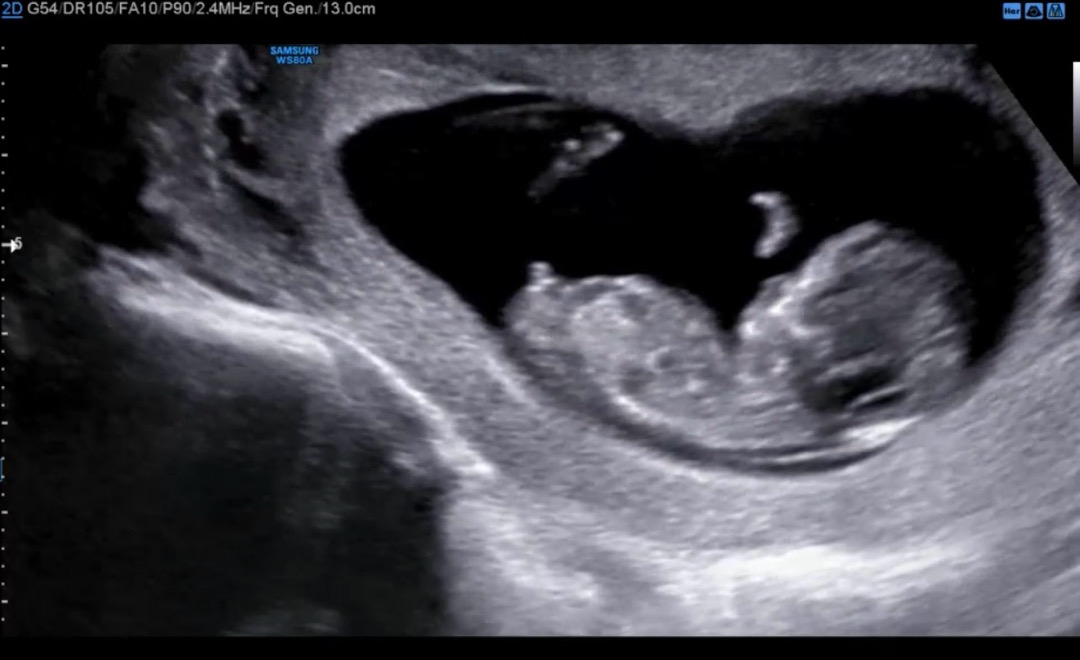

성별 의견부탁드려용

난황위치랑 심소리는 딸 같앗는데 각도법은 아들일까요.?!

병원에서 각도법이 그나마 제일 정확하다셨어요! 나머지는 다 미신이라셨구요 특히 난황위치는 병원마다 촘파보는 각도에따라 다르다셨구 심소도 과학적으로 전혀 근거없는 이야기러셨구용 ㅎㅎㅎ 저두 아들같아요!

아들 같네요 ! ㅎㅎ100프로정답은 아니겠지만 척추랑 평행되면 딸이라던데 아가는 살짝 위로 향한듯해여! ㅎㅎ